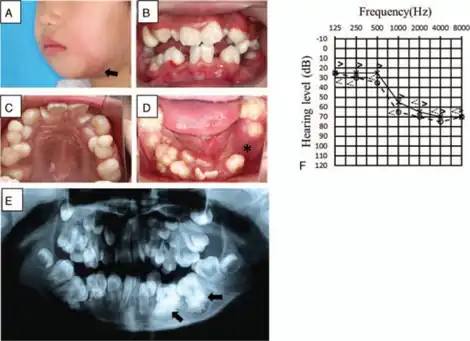

Otodental syndrome, also known as otodental dysplasia, is an exceptionally rare disease that is distinguished by a specific phenotype known as globodontia, that in rare cases can be associated with eye coloboma and high frequency hearing loss. Globodontia is an abnormal condition that can occur in both the primary and secondary dentition, except for the incisors which are normal in shape and size.[1][2][3] This is demonstrated by significant enlargement of the canine and molar teeth.[1] The premolars are either reduced in size or are absent.[3] In some cases, the defects affecting the teeth, eye and ear can be either individual or combined.[4] When these conditions are combined with eye coloboma, the condition is also known as oculo-otodental syndrome. The first known case of otodental syndrome was found in Hungary in a mother and her son by Denes and Csiba in 1969.[5] Prevalence is less than 1 out of every 1 million individuals.[2] The cause of otodental syndrome is considered to be genetic. It is an autosomal dominant inheritance and is variable in its expressivity.[6] Haploinsufficiency in the fibroblast growth factor 3 (FGF3) gene (11q13) has been reported in patients with otodental syndrome and is thought to cause the phenotype.[2] Both males and females are equally affected. Individuals diagnosed with otodental syndrome can be of any age; age is not a relevant factor. Currently there are no specific genetic treatments for otodental syndrome. Dental and orthodontic management are the recommended course of action.[1]

- Globodontia – an abnormal condition that can occur in both primary and secondary tooth development, in which the molars and canines are greatly enlarged. It refers to the enlarged bulbous fused malformed posterior teeth with almost no discernible cusps or grooves.[1] The molars are known to have a rounded globe-like shape. Can attribute to pain.

- Taurodontism – known as a condition in which the body of a tooth is enlarged at the expense of the roots. This results in an enlarged pulp chamber, lack of proper bonding at the cementoenamel junction, and can cause the pulpal floor to be displaced towards the root.[8] Discomfort and pain are usually associated with these characteristics.

Diagnosis of otodental syndrome was established using clinical, histopathological and audiometric methodologies.[4] In normal individuals, by the age of 2-3, radiograph images should depict any signs of premolar development. A formal diagnosis of no premolar growth can be done by age 6 in order to check for signs of otodental syndrome.[3] Sensorineural hearing loss can be another measure for proper diagnosis as well as checking for ocular coloboma. The latter is usually noticed at an around birth.